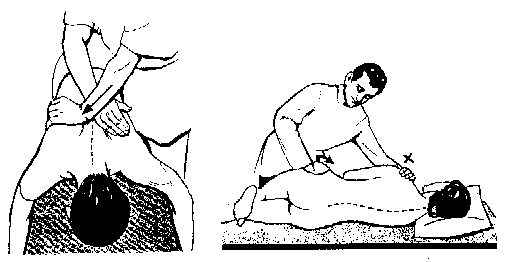

Tratamentul balneofizioterapeutic in spondiloza dorsala

Definitie si generalitati Spondiloza dorsala (dorsartroza sau dorsalgia) reprezinta localizarea procesului degenerativ la nivelul coloanei dorsale, atat in sectorul discosomatic cat si interapofizar; pot exista si la acest nivel manifestarCiteste tot ... 2105 cuvinte

Dimensiune medie

+ cu poze |